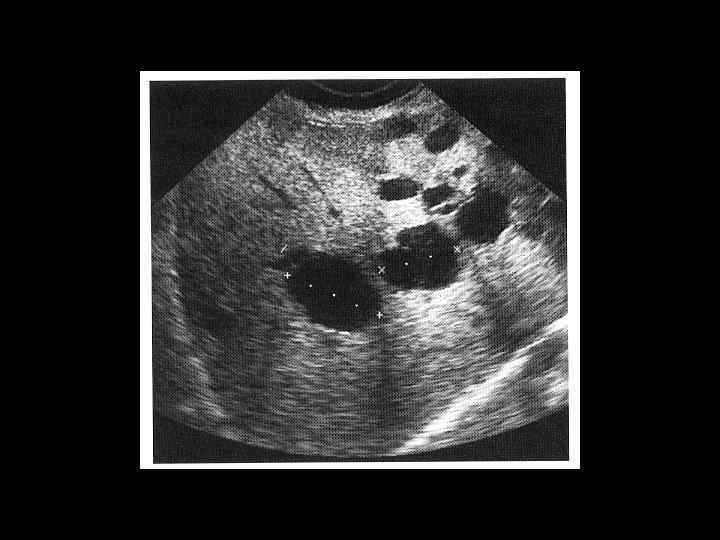

АКТУАЛЬНЫЕ ВОПРОСЫ РЕНТГЕНОЛОГИИ ЛУЧЕВАЯ ДИАГНОСТИКА ОЧАГОВЫХ ПОРАЖЕНИЙ ПЕЧЕНИ КИСТЫ ПЕЧЕНИ Ультразвуковая семиотика: - эхонегативное образование - четкая граница - тонкие стенки - периферическое усиление эхосигнала

АКТУАЛЬНЫЕ ВОПРОСЫ РЕНТГЕНОЛОГИИ ЛУЧЕВАЯ ДИАГНОСТИКА ОЧАГОВЫХ ПОРАЖЕНИЙ ПЕЧЕНИ КИСТЫ ПЕЧЕНИ Компьютерно-томографическая семиотика: - образования низкоплотностные (близкие к плотности воды) - округлой формы - с четкими, ровными, дугообразными контурами - не отмечается усиление стенок и содержимого после контрастирования

АКТУАЛЬНЫЕ ВОПРОСЫ РЕНТГЕНОЛОГИИ ЛУЧЕВАЯ ДИАГНОСТИКА ОЧАГОВЫХ ПОРАЖЕНИЙ ПЕЧЕНИ КИСТЫ ПЕЧЕНИ МР семиотика: - образования с гиперинтенсивным сигналом, четкими, ровными контурами